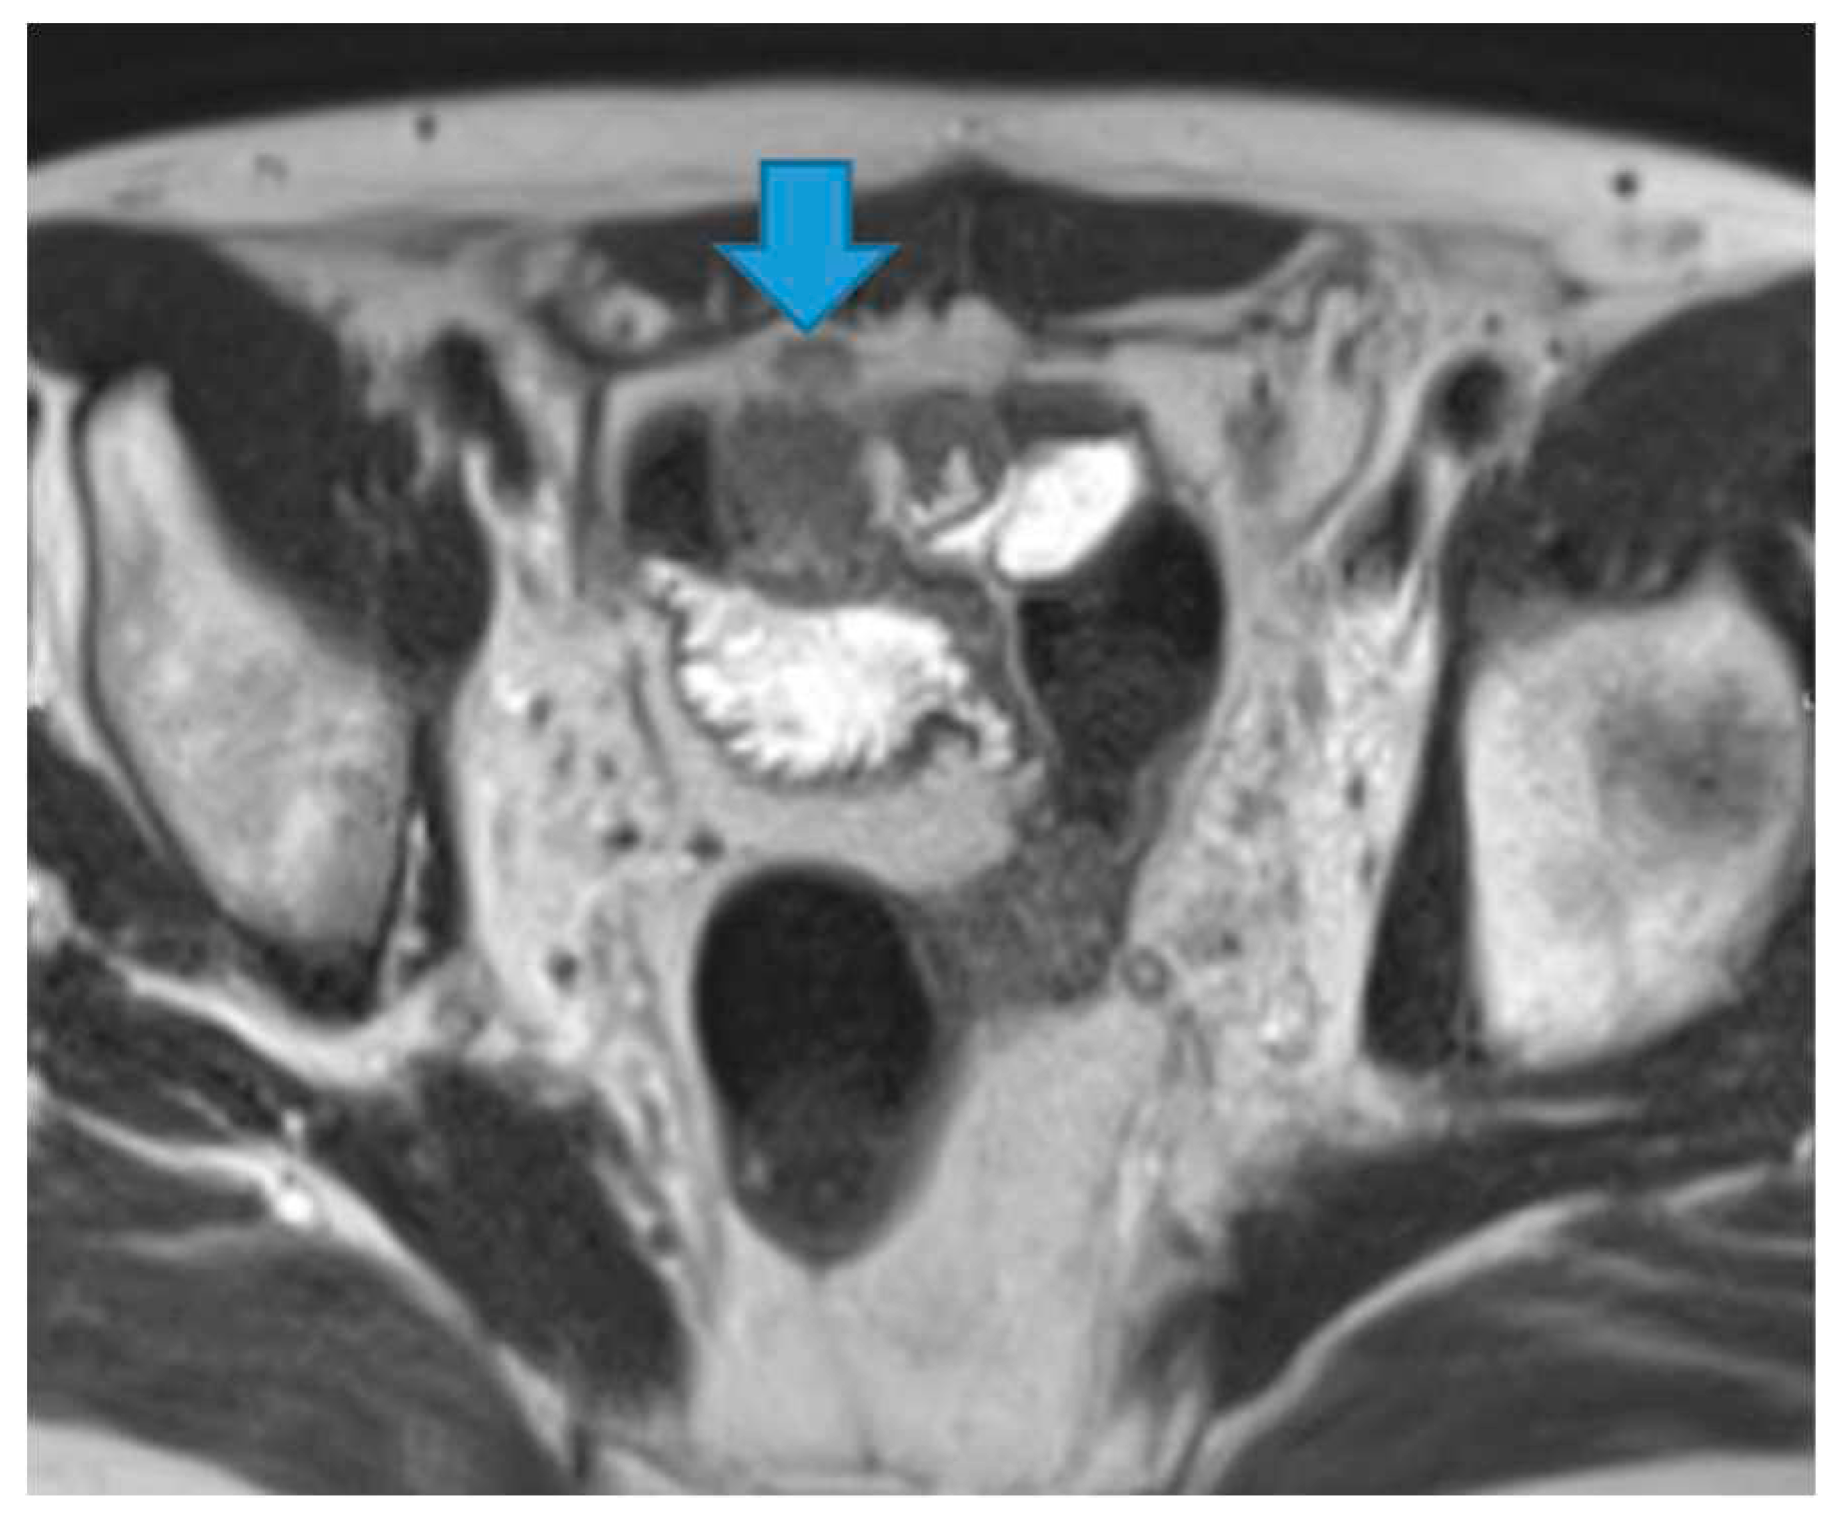

Figure 36.

Axial CE-CT (A). PC from sigmoid adenocarcinoma: Bilateral ovarian metastasis as complex cystic masses with solid poles. Axial CE-CT (B, D). PC from colon adenocarcinoma: Bilateral ovarian metastasis as solid masses. Axial T2WI (C). PC from mucinous tumour of the appendix: Left ovarian metastases (*) presenting as a predominantly hyperintense mass due to the mucin content.

Another common site of PC in the pelvis is the ovaries. As seen previously, they are extraperitoneal organs but considered intraperitoneal as they communicate with the peritoneal cavity. This is the reason why ovaries are included amongst the locations of PC.

Compared to primary ovarian tumours, ovarian metastases seem to be smaller, more frequently bilateral, showing more uniform cysts and more moderate enhancement of the solid portions [

18]. Although a solid appearance may also be found or even characteristics resembling the primary tumour (

Figure 36).

The term Krukenberg tumour is sometimes misused in the setting of ovarian metastases from a gastrointestinal tumour, as its use should be limited to ovarian metastasis from a poorly differentiated adenocarcinoma with signet ring cell features [

19]. Krukenberg tumour should be considered in the differential diagnosis when solid bilateral ovarian masses containing intratumoral cystic component are detected, even in the absence of a primary malignancy [

20].